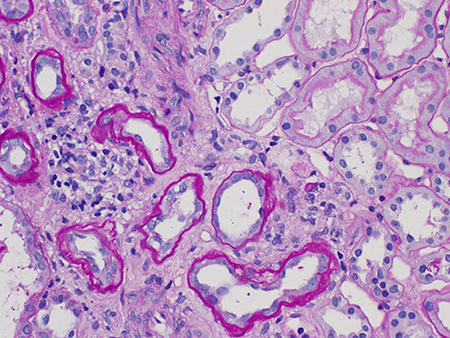

Tubular atrophy/interstitial fibrosis (T0, T1, or T2).[Figure caption and citation for the preceding image starts]: Tubular atrophy and interstitial fibrosis in IgA nephropathy (the atrophied tubules are seen on the left of the field, and normal tubules are seen on the right) (Periodic acid-Schiff stain, x400)Courtesy of Drs Hwei Yee Lee, Cristine Ding, and Yong Howe Ho (Tan Tock Seng Hospital, Singapore) [Citation ends].